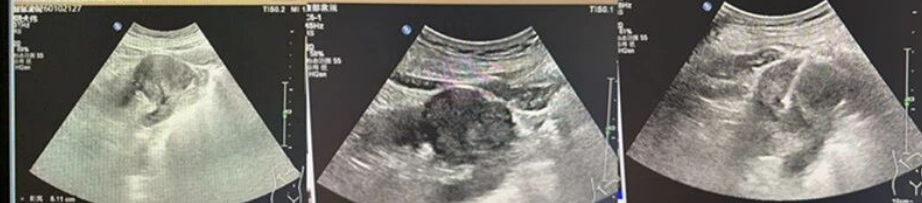

接診醫(yī)生詳細(xì)詢問病史后,為其安排腹部超聲檢查,在右腎中段發(fā)現(xiàn)一處向外凸起的不均質(zhì)低實(shí)性回聲,大小約5.1×4.3cm,形態(tài)欠規(guī)則、邊界尚清,CDFI顯示病灶內(nèi)可見低速低阻型動(dòng)脈血流信號(hào),超聲提示右腎占位、考慮惡性,建議進(jìn)一步行超聲引導(dǎo)下腎腫物穿刺活檢明確性質(zhì)。次日,我院為范大爺完成穿刺活檢,病理結(jié)果確診為腎透明細(xì)胞癌,結(jié)合腰椎CT檢查,最終診斷為腎透明細(xì)胞癌伴腰椎轉(zhuǎn)移。